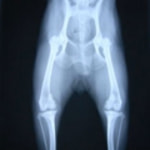

■ 症例20 ポメラニアン 8ヶ月 1.8kg

左右膝蓋骨脱臼 グレードⅢ

2ヶ月前から間欠的跛行が認められ、両膝の膝蓋骨脱臼整復術を行った。

手技は縫工筋及び内側広筋の解放、脛骨粗面の外側転位、滑車ブロック形造溝術、内外側関節包の縫縮を選択し実施した。

右側の膝蓋骨脱臼は上記手技で整復されたものの、左側はそれのみでは膝蓋骨が浮く様子が認められた。その為、PDS縫合糸にて膝蓋靱帯を1糸のみ縫合し、靱帯の縫縮を行った。